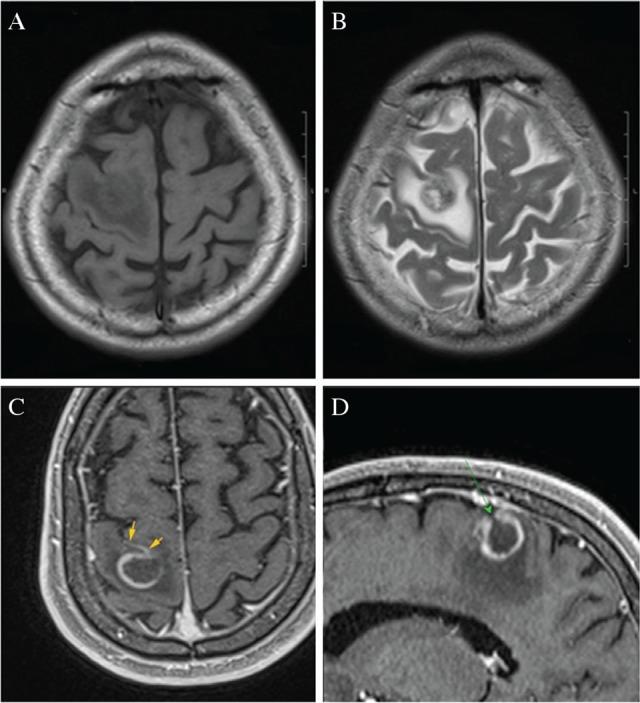

Sarcoidosis is occasionally associated with malignant lymphoma. Cases of sarcoidosis associated with malignant lymphoma are called sarcoidosis-lymphoma syndrome. We report a 63-year-old man with sarcoidosis associated with primary central nervous system lymphoma (PCNSL). Definitive diagnosis by clinical and radiological findings was difficult. Finally, brain biopsy could produce the correct diagnosis. We could provide appropriate treatment for PCNSL and the patient has survived over 2 years. Thus, it is very important to make an early definitive diagnosis by biopsy for intracranial lesion, because it can prolong survival in patients with sarcoidosis.

结节病偶尔与恶性淋巴瘤相关。与恶性淋巴瘤相关的结节病病例被称为结节病 - 淋巴瘤综合征。我们报告一名63岁患有结节病并伴有原发性中枢神经系统淋巴瘤(PCNSL)的男性。通过临床和影像学检查结果进行明确诊断很困难。最后,脑活检得以做出正确诊断。我们能够为PCNSL提供适当的治疗,患者已存活超过2年。因此,通过活检对颅内病变进行早期明确诊断非常重要,因为这可以延长结节病患者的生存期。